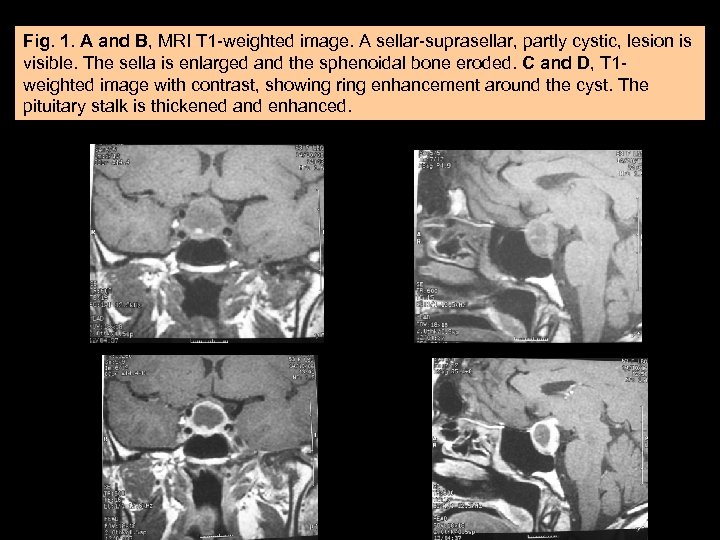

Case Report. • A 53 years-old woman presented with acute diabetes insipidus and visual impairment. • At imaging (MRI), there was an intense contrastenhancing intra-supra-sellar mass with a large cystic component compressing the optic chiasm and the pituitary stalk.

Fig. 1. A and B, MRI T 1 -weighted image. A sellar-suprasellar, partly cystic, lesion is visible. The sella is enlarged and the sphenoidal bone eroded. C and D, T 1 weighted image with contrast, showing ring enhancement around the cyst. The pituitary stalk is thickened and enhanced. A C B D